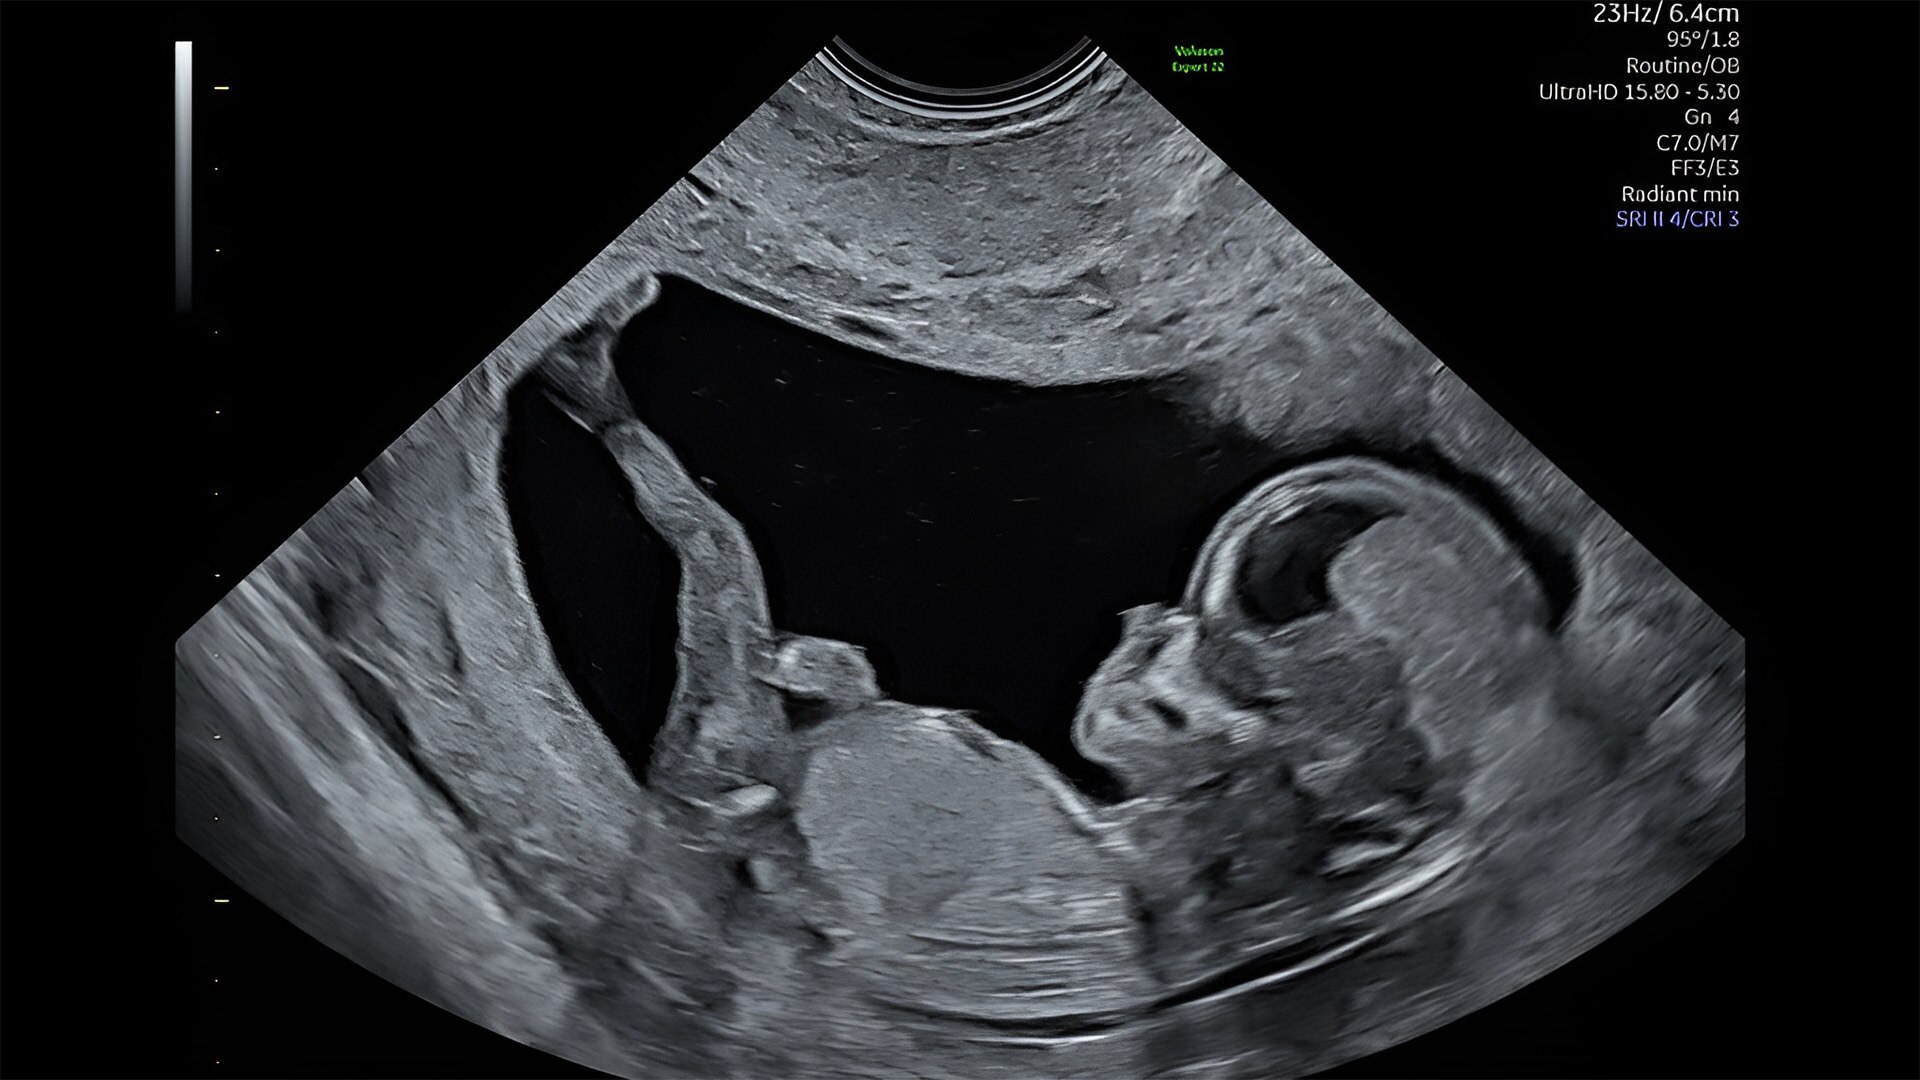

First trimester exams

Perform detailed exams with high-resolution for early insights to fetal health

Complex cases come with enough uncertainty. That's why the Voluson Expert 22 is specifically designed for in-depth assessment of complicated anatomy — with pioneering first trimester, fetal cardiac, gynecological, and other pivotal technologies that focus on early detection and intervention.